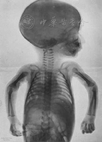

1896年1月23日,伦琴首次向外界展示自己的"X射线管"。1月27日,耶鲁大学的年轻医生亚瑟·赖特(Arthur Wright)实验性地成功拍摄了一张X光片[7],当时美国生理学家坎农(Walter Bradford Cannon)还是哈佛大学医学院的学生,他最早开始用荧光屏跟随钡剂通过动物的消化系统进行研究,这可能与托马斯·阿尔瓦·爱迪生发明X射线荧光屏是同一年[8]。1月29日,美国人格拉布(Émil H. Grubbe)等[9]首次将X射线用于皮肤癌的治疗;2月3日,美国的埃德温(Edwin Frost)兄弟和加拿大的考克斯(John Cox)先后将X射线机用于疾病的诊断,同月有人用X射线第一次拍摄到了子宫内胎儿的图像[1,10]。1896年2月7日,在英格兰的利物浦大学,医生为一个12岁的男孩探察手腕中子弹位置(枪伤),并确认子弹在第三腕掌关节[11]。图4是1896年5月不正当应用情况下拍摄的幼儿X射线照片,该照片当时发表在临床投影档案杂志[12]。图5是德国人1896年设计的用于观察手部骨骼损伤的简易X射线荧光镜[12]。